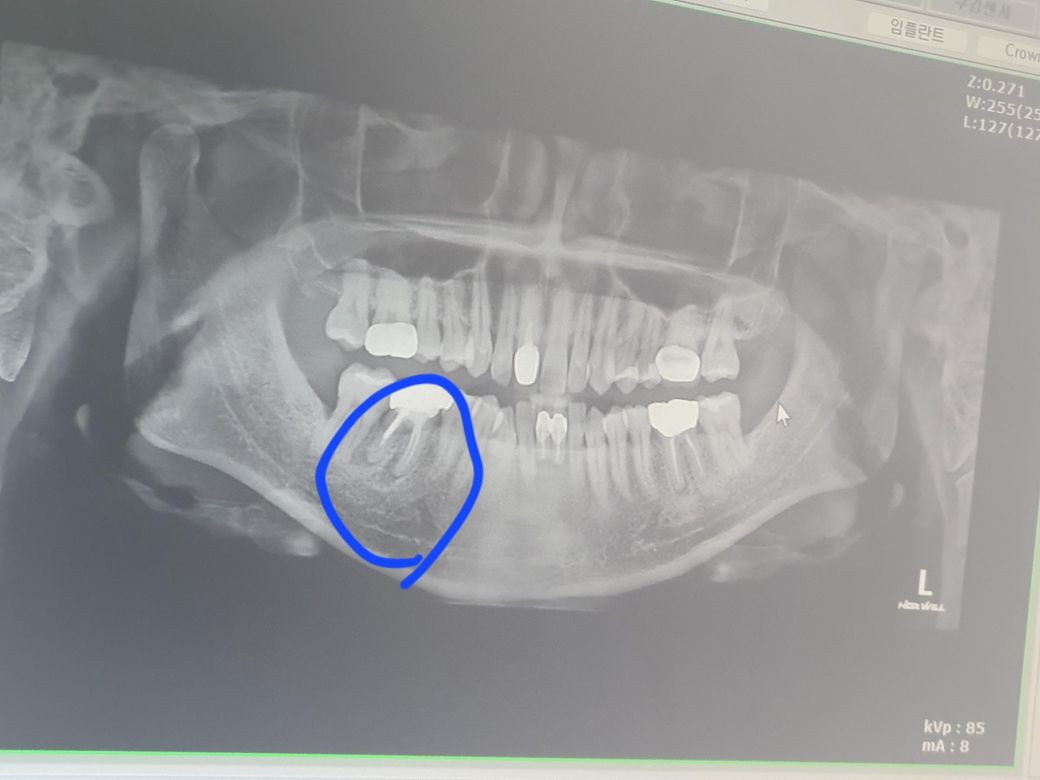

이 치근단농양일까요?? 치료 또는 발치 알려주세요

뿌리쪽까지 손상가서 기둥세우고 한 20년쓴 이 입니다

치아 뿌리끝에 염증이 있긴하지만 활성화된 상태는 아니라서 일단은 잇몸치료 하면서 관리하시는게 좋을것같습니다.

엑스레이 사진으로나 임상사진으로나 농양이 잡혀있는 상태입니다. 재신경치료, 치근단절제술을 시도해볼 순 있으나 발치 가능성이 높습니다.